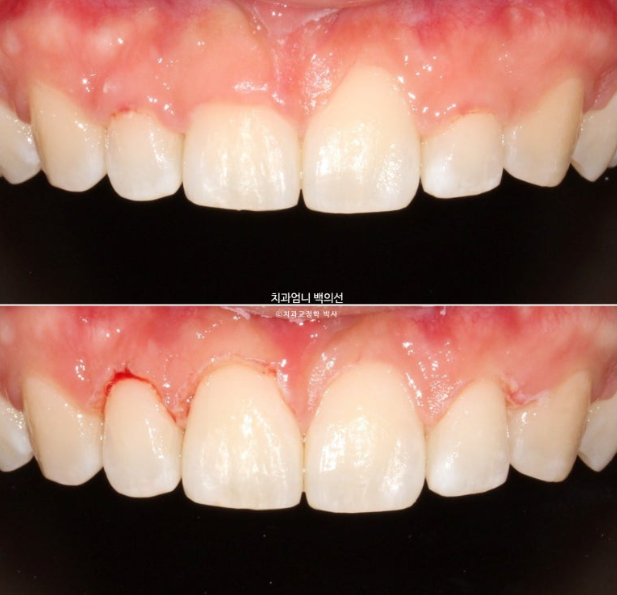

25.01

잇몸성형 직후 사진입니다.

잇몸이 부어있던 곳에서만 피가 조금 나고 다른 곳은 출혈이 없습니다.